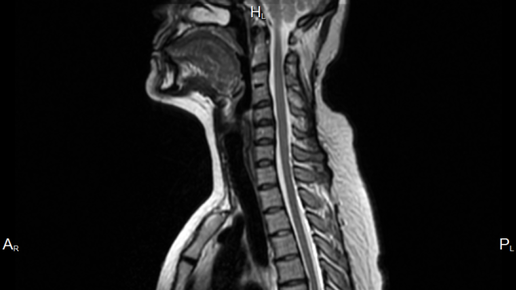

МРТ позвоночника - это томографическое комплексное обследование различных зон позвоночного столба. Магнитно-резонансный метод диагностики может с точностью определить даже мельчайшие повреждения в позвоночнике, чтобы начать своевременное и правильное лечение...

Здравствуйте, уважаемые читатели! Сегодня мы обсудим такую важную тему, как магнитно-резонансная томография (МРТ) позвоночника. Это исследование помогает врачам получить детальные изображения структур вашего позвоночника и выявить различные заболевания. Давайте разберемся, когда назначают МРТ и что оно может показать. «Здоровье — это состояние, в котором тело, разум и дух работают в гармонии». Давайте вместе позаботимся о том, чтобы наше здоровье было в порядке! МРТ позвоночника может быть рекомендовано...